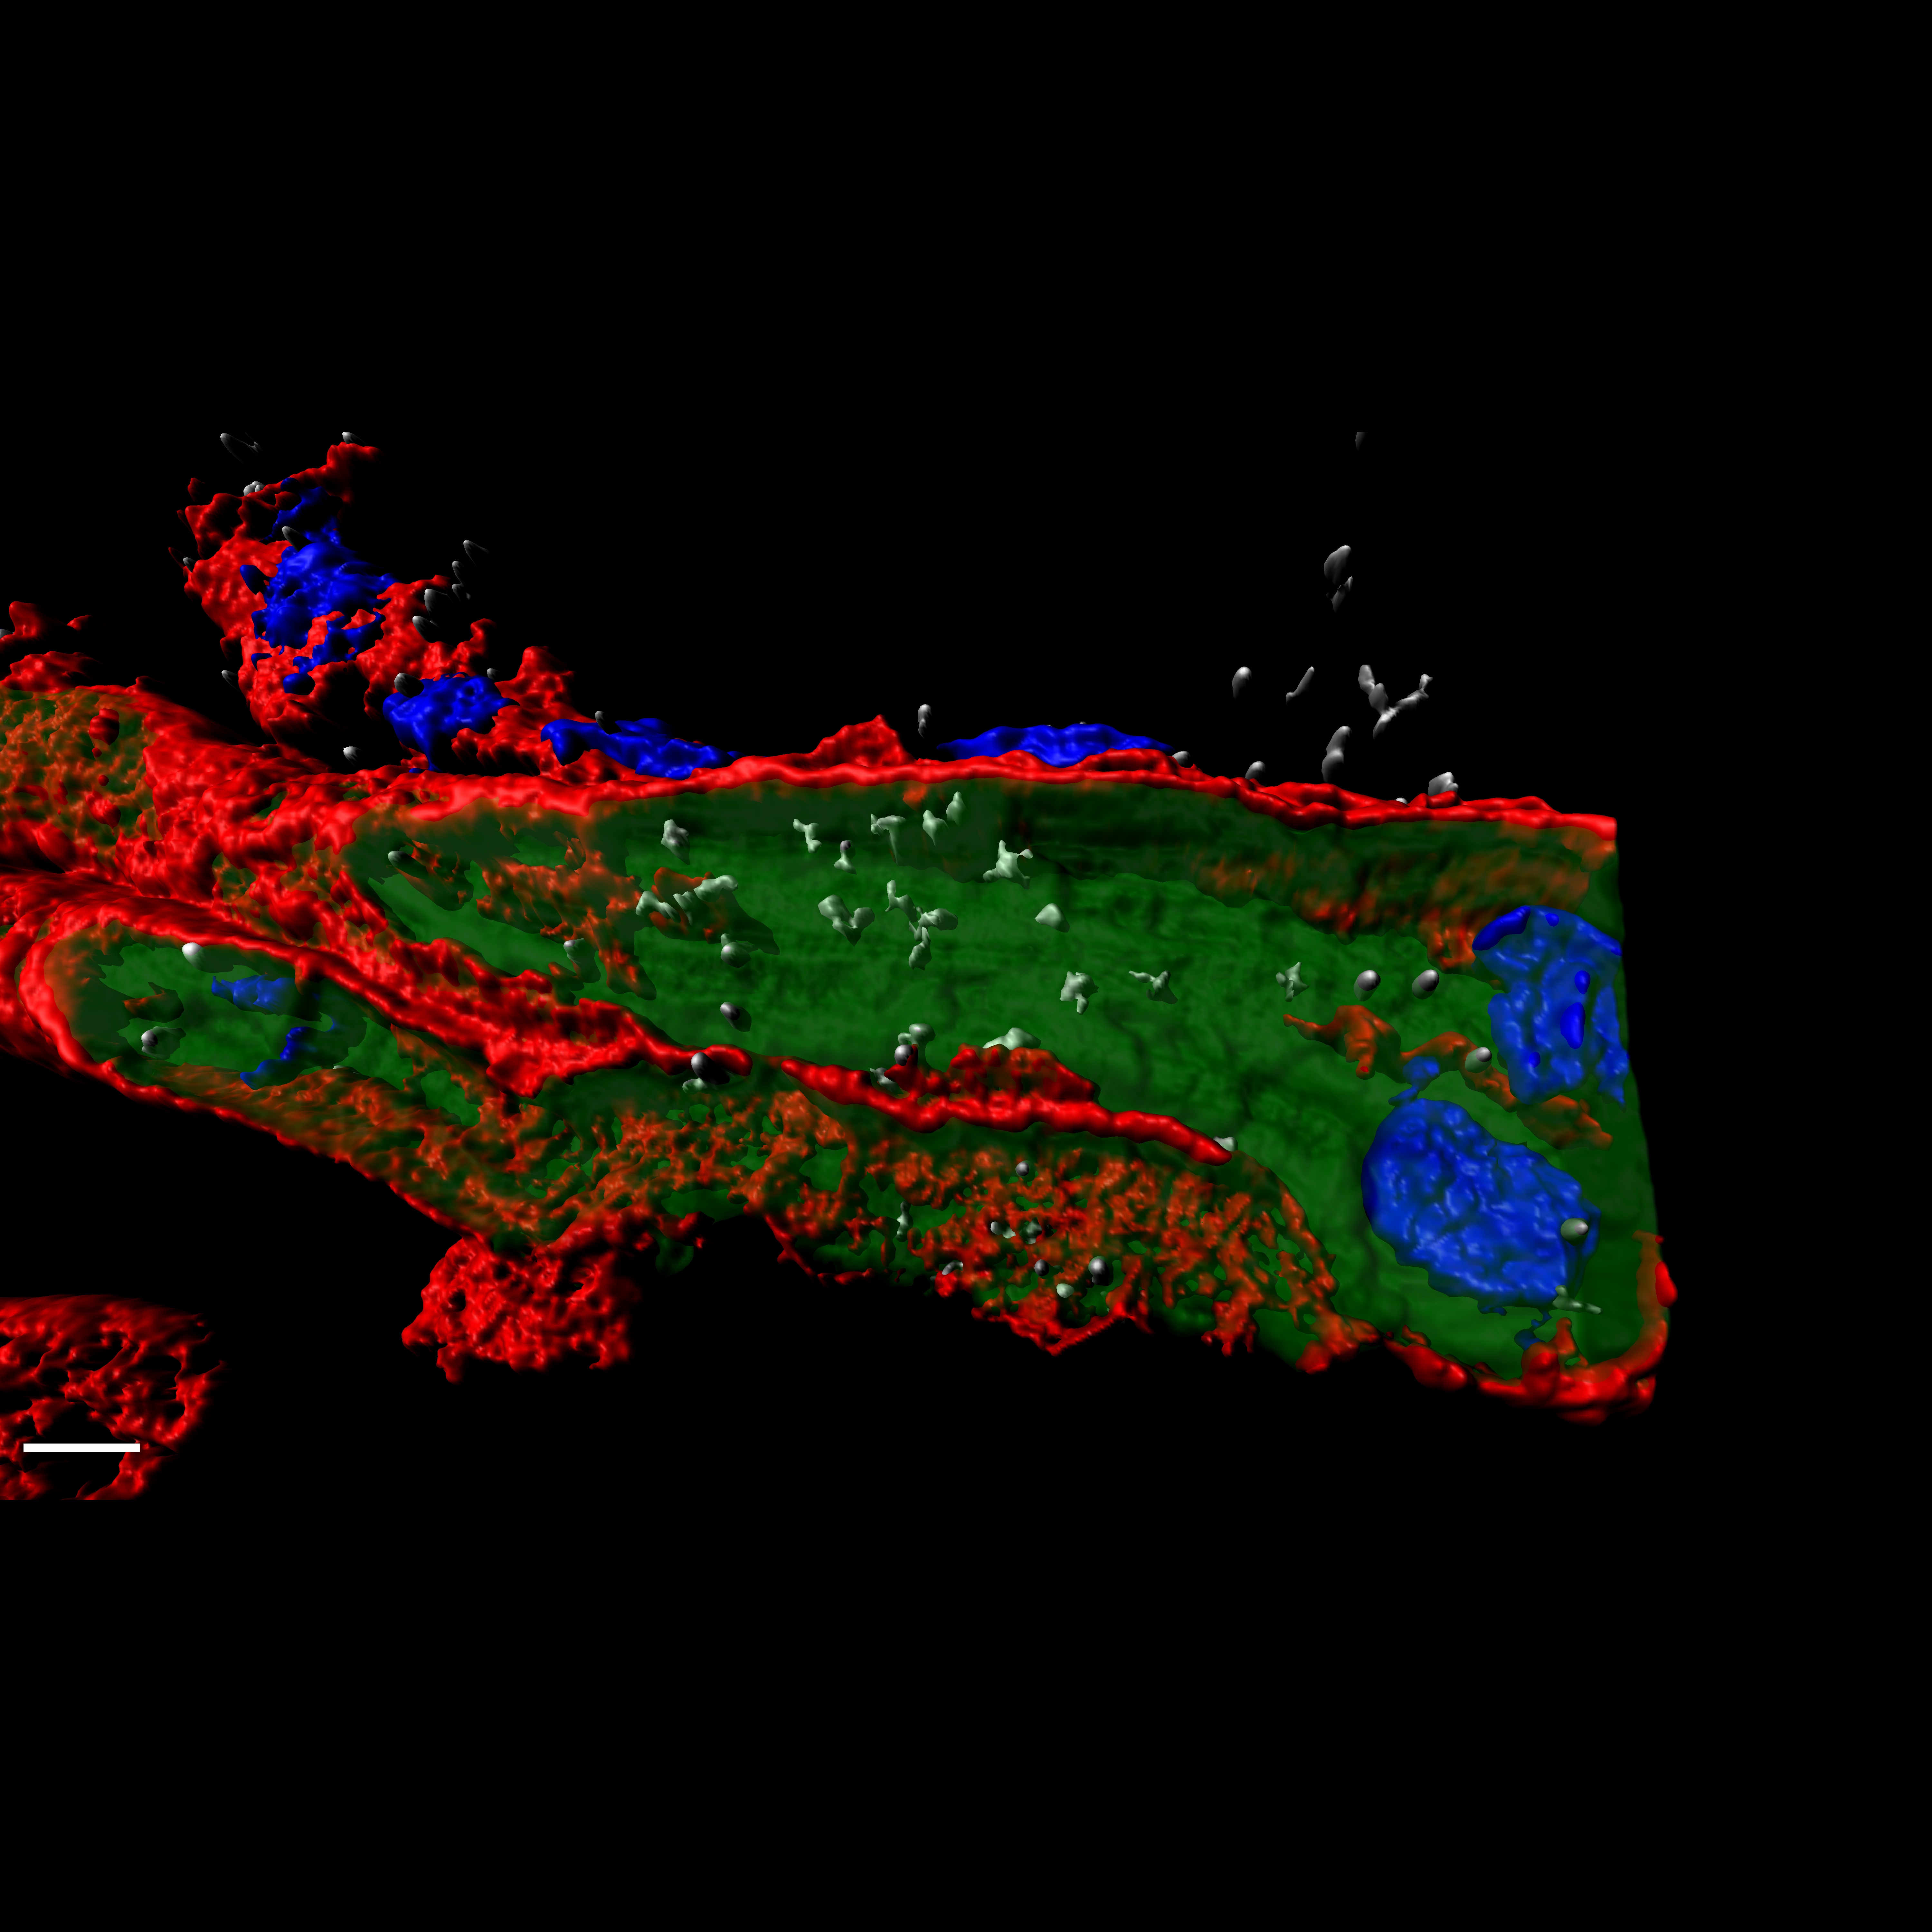

• CIBERER

Un producto de terapias avanzadas que combina edición genómica y bioingeniería tisular, designado medicamento huérfano para la piel de mariposa

06/05/2020